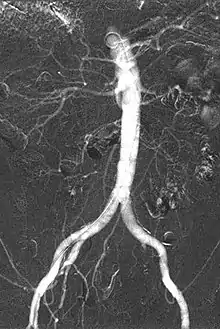

CO2 Angiogram showing Abdominal Aorta, visceral arteries and iliac arteries